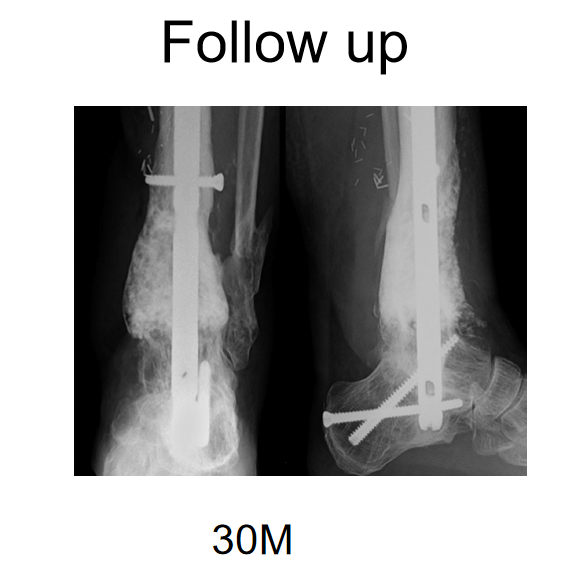

膜诱导重建可加速骨愈合,患者术后早期可完全负重。虽然不同文献报道膜诱导重建术后骨愈合时间不一,但影像学检查示骨愈合时间一般为4~8个月。Yeganeh等研究发现,年龄、骨缺损长度和感染时间均对骨缺损修复无影响,但可能与植骨材料中自体骨的含量过低、骨折固定方式、低毒力细菌感染等相关。当膜诱导重建过程中发生骨延迟愈合后,不要急于外科干预,可指导患者行负重训练,其中一部分患者可在骨移植术后1~2年缓慢愈合(图7)。当内固定已失效或等待时间超过2年时,可考虑再次手术干预。

图7 膜诱导重建过程中发生骨延迟愈合,可行负重训练,其中一部分患者可在骨移植术后1~2年缓慢愈合 A,B 膜诱导重建术后1年正、侧位X线片示植骨区成骨不全,近端发生骨不连 C,D 术后2年,正、侧位X线片示移植骨塑形良好